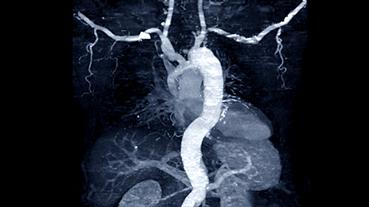

In 2025, cardiologists and cardiac surgeons at NewYork-Presbyterian led breakthroughs that impacted a range of diseases and conditions from advanced heart failure to pediatric valve disease. Physicians and researchers from Columbia and Weill Cornell Medicine pioneered the use of artificial intelligence to identify structural heart disease, launched a mobile app to expand access to heart failure education, performed one of the first split-root domino partial heart transplants, and more. Our experts remained at the forefront of innovative, multidisciplinary care, delivering comprehensive treatment for the most complex cardiac diseases.

Our world-renowned Columbia and Weill Cornell Medicine physicians and surgeons in our comprehensive cardiology, heart surgery, and vascular programs spearhead groundbreaking clinical and scientific research and provide the most innovative treatments to optimize patient outcomes for all stages of disease complexity. Our clinicians are experts in minimally invasive approaches and novel therapeutics for all types of heart disease and work across disciplines to provide compassionate care to all patients.